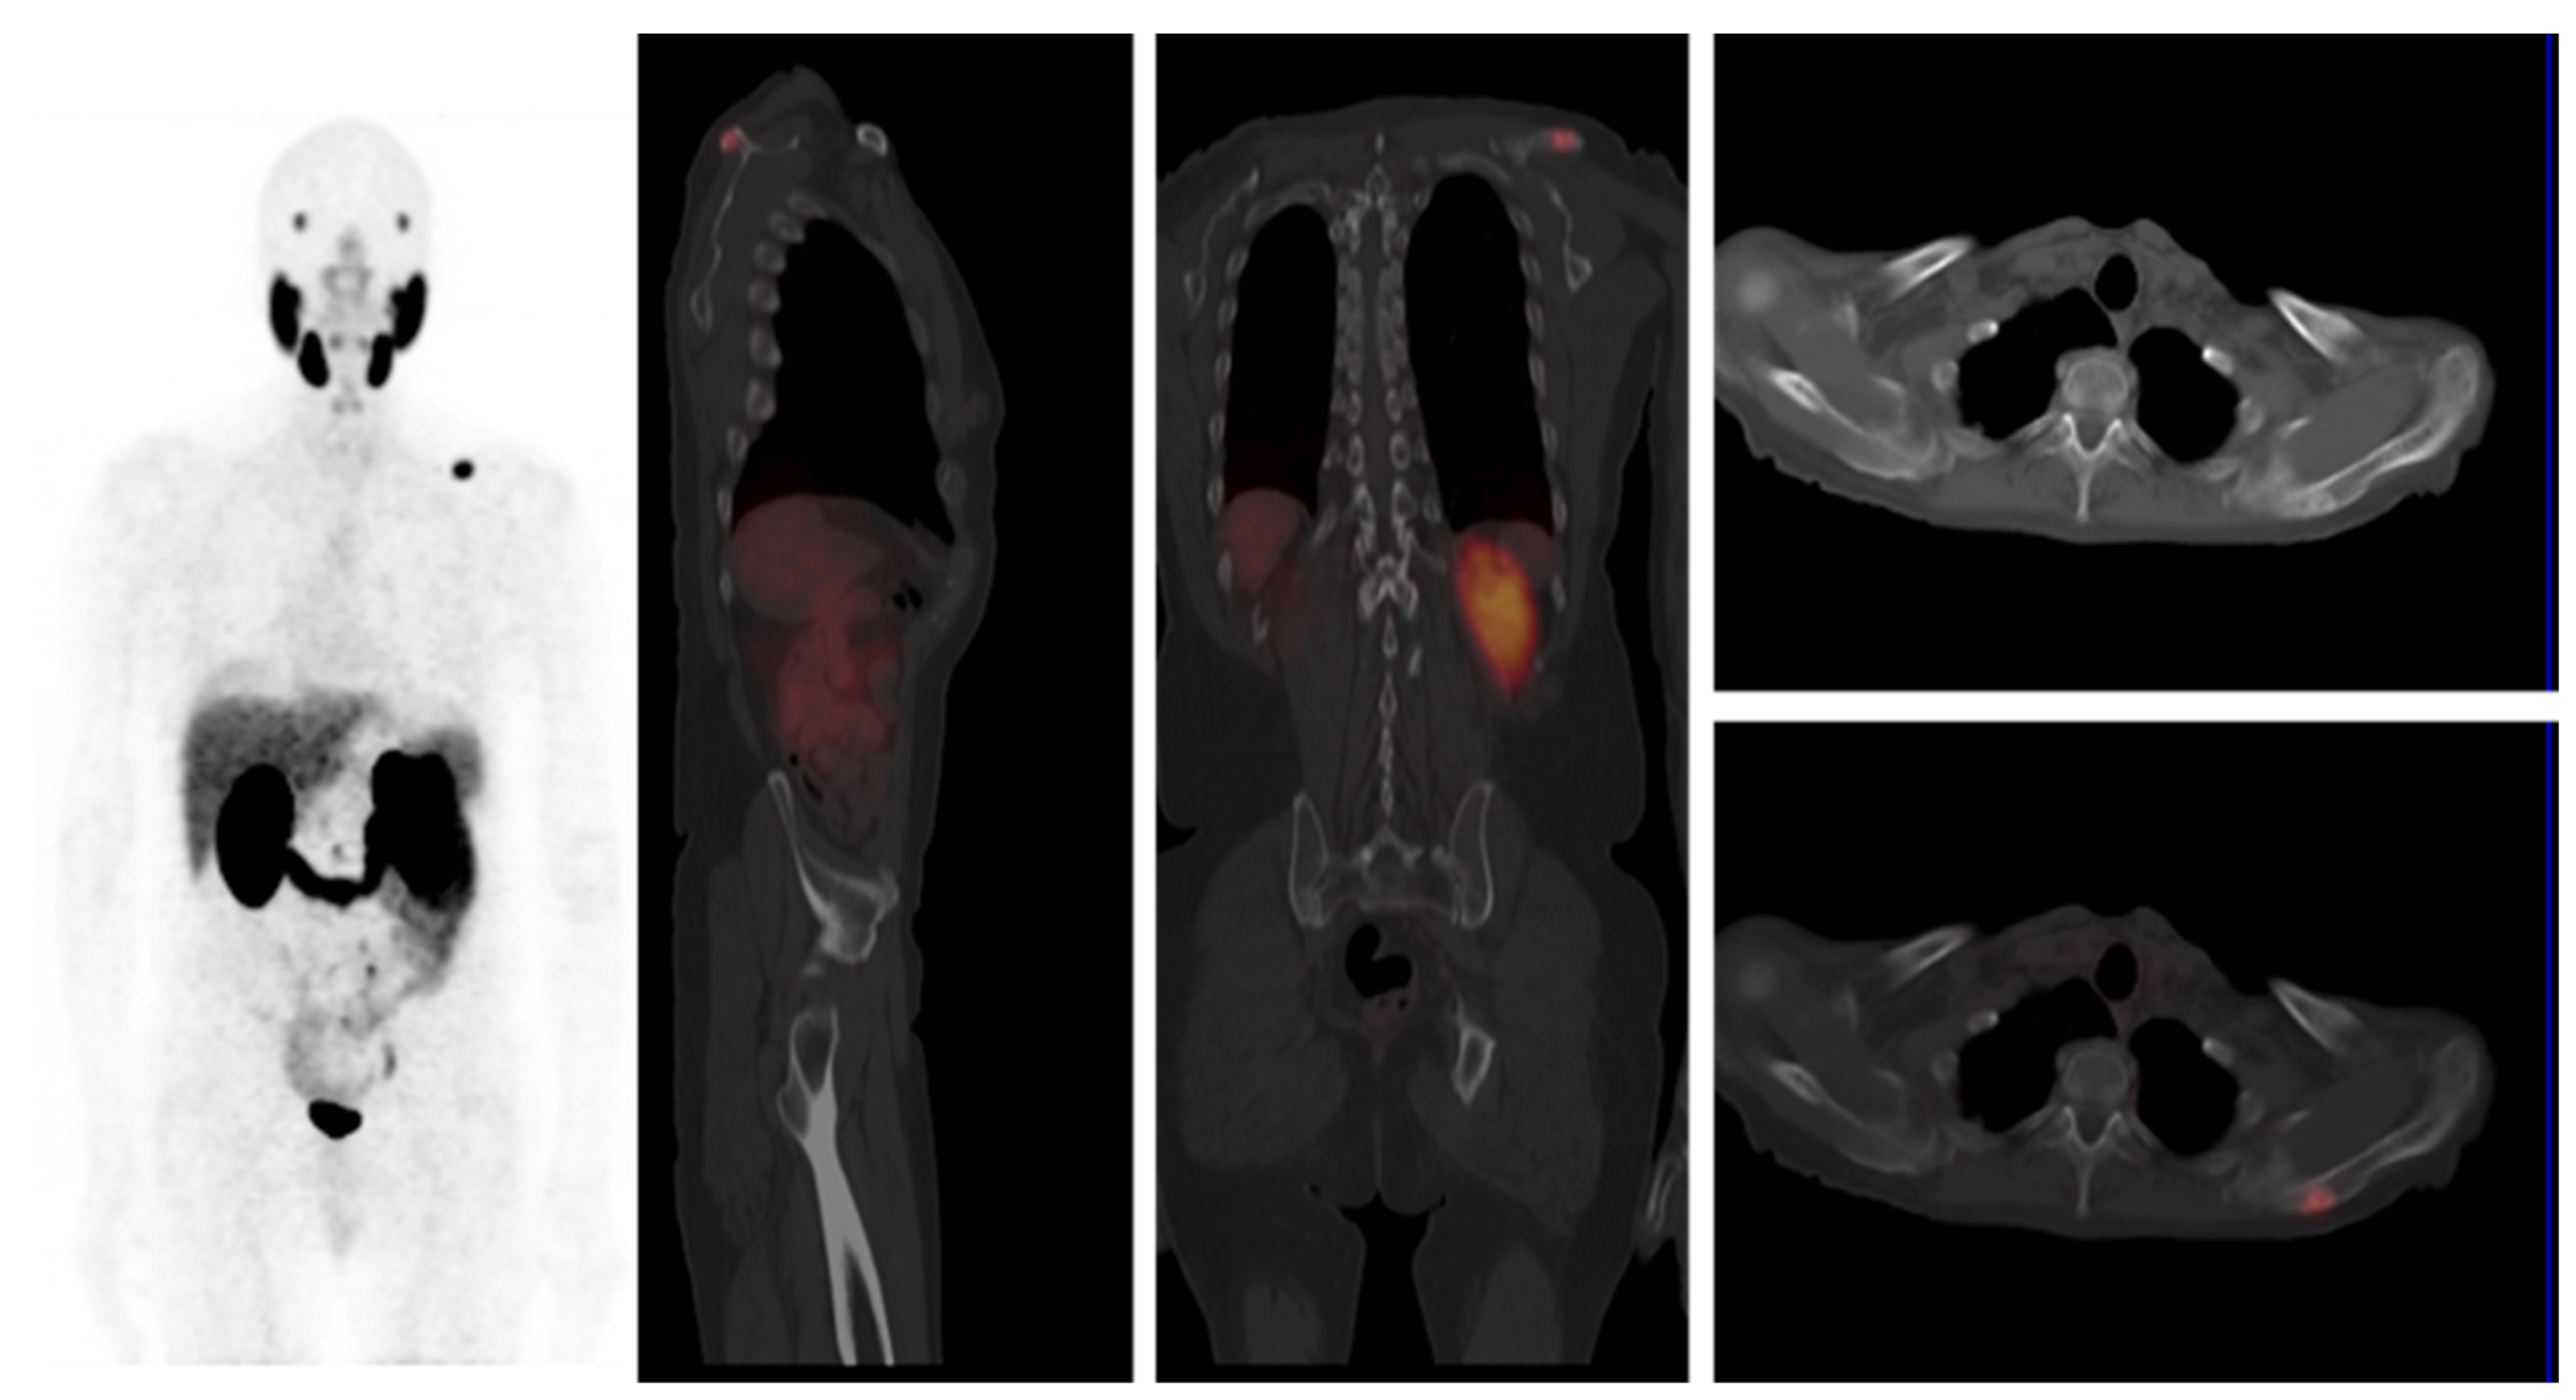

3.1. Pattern of Prostate Cancer Recurrence